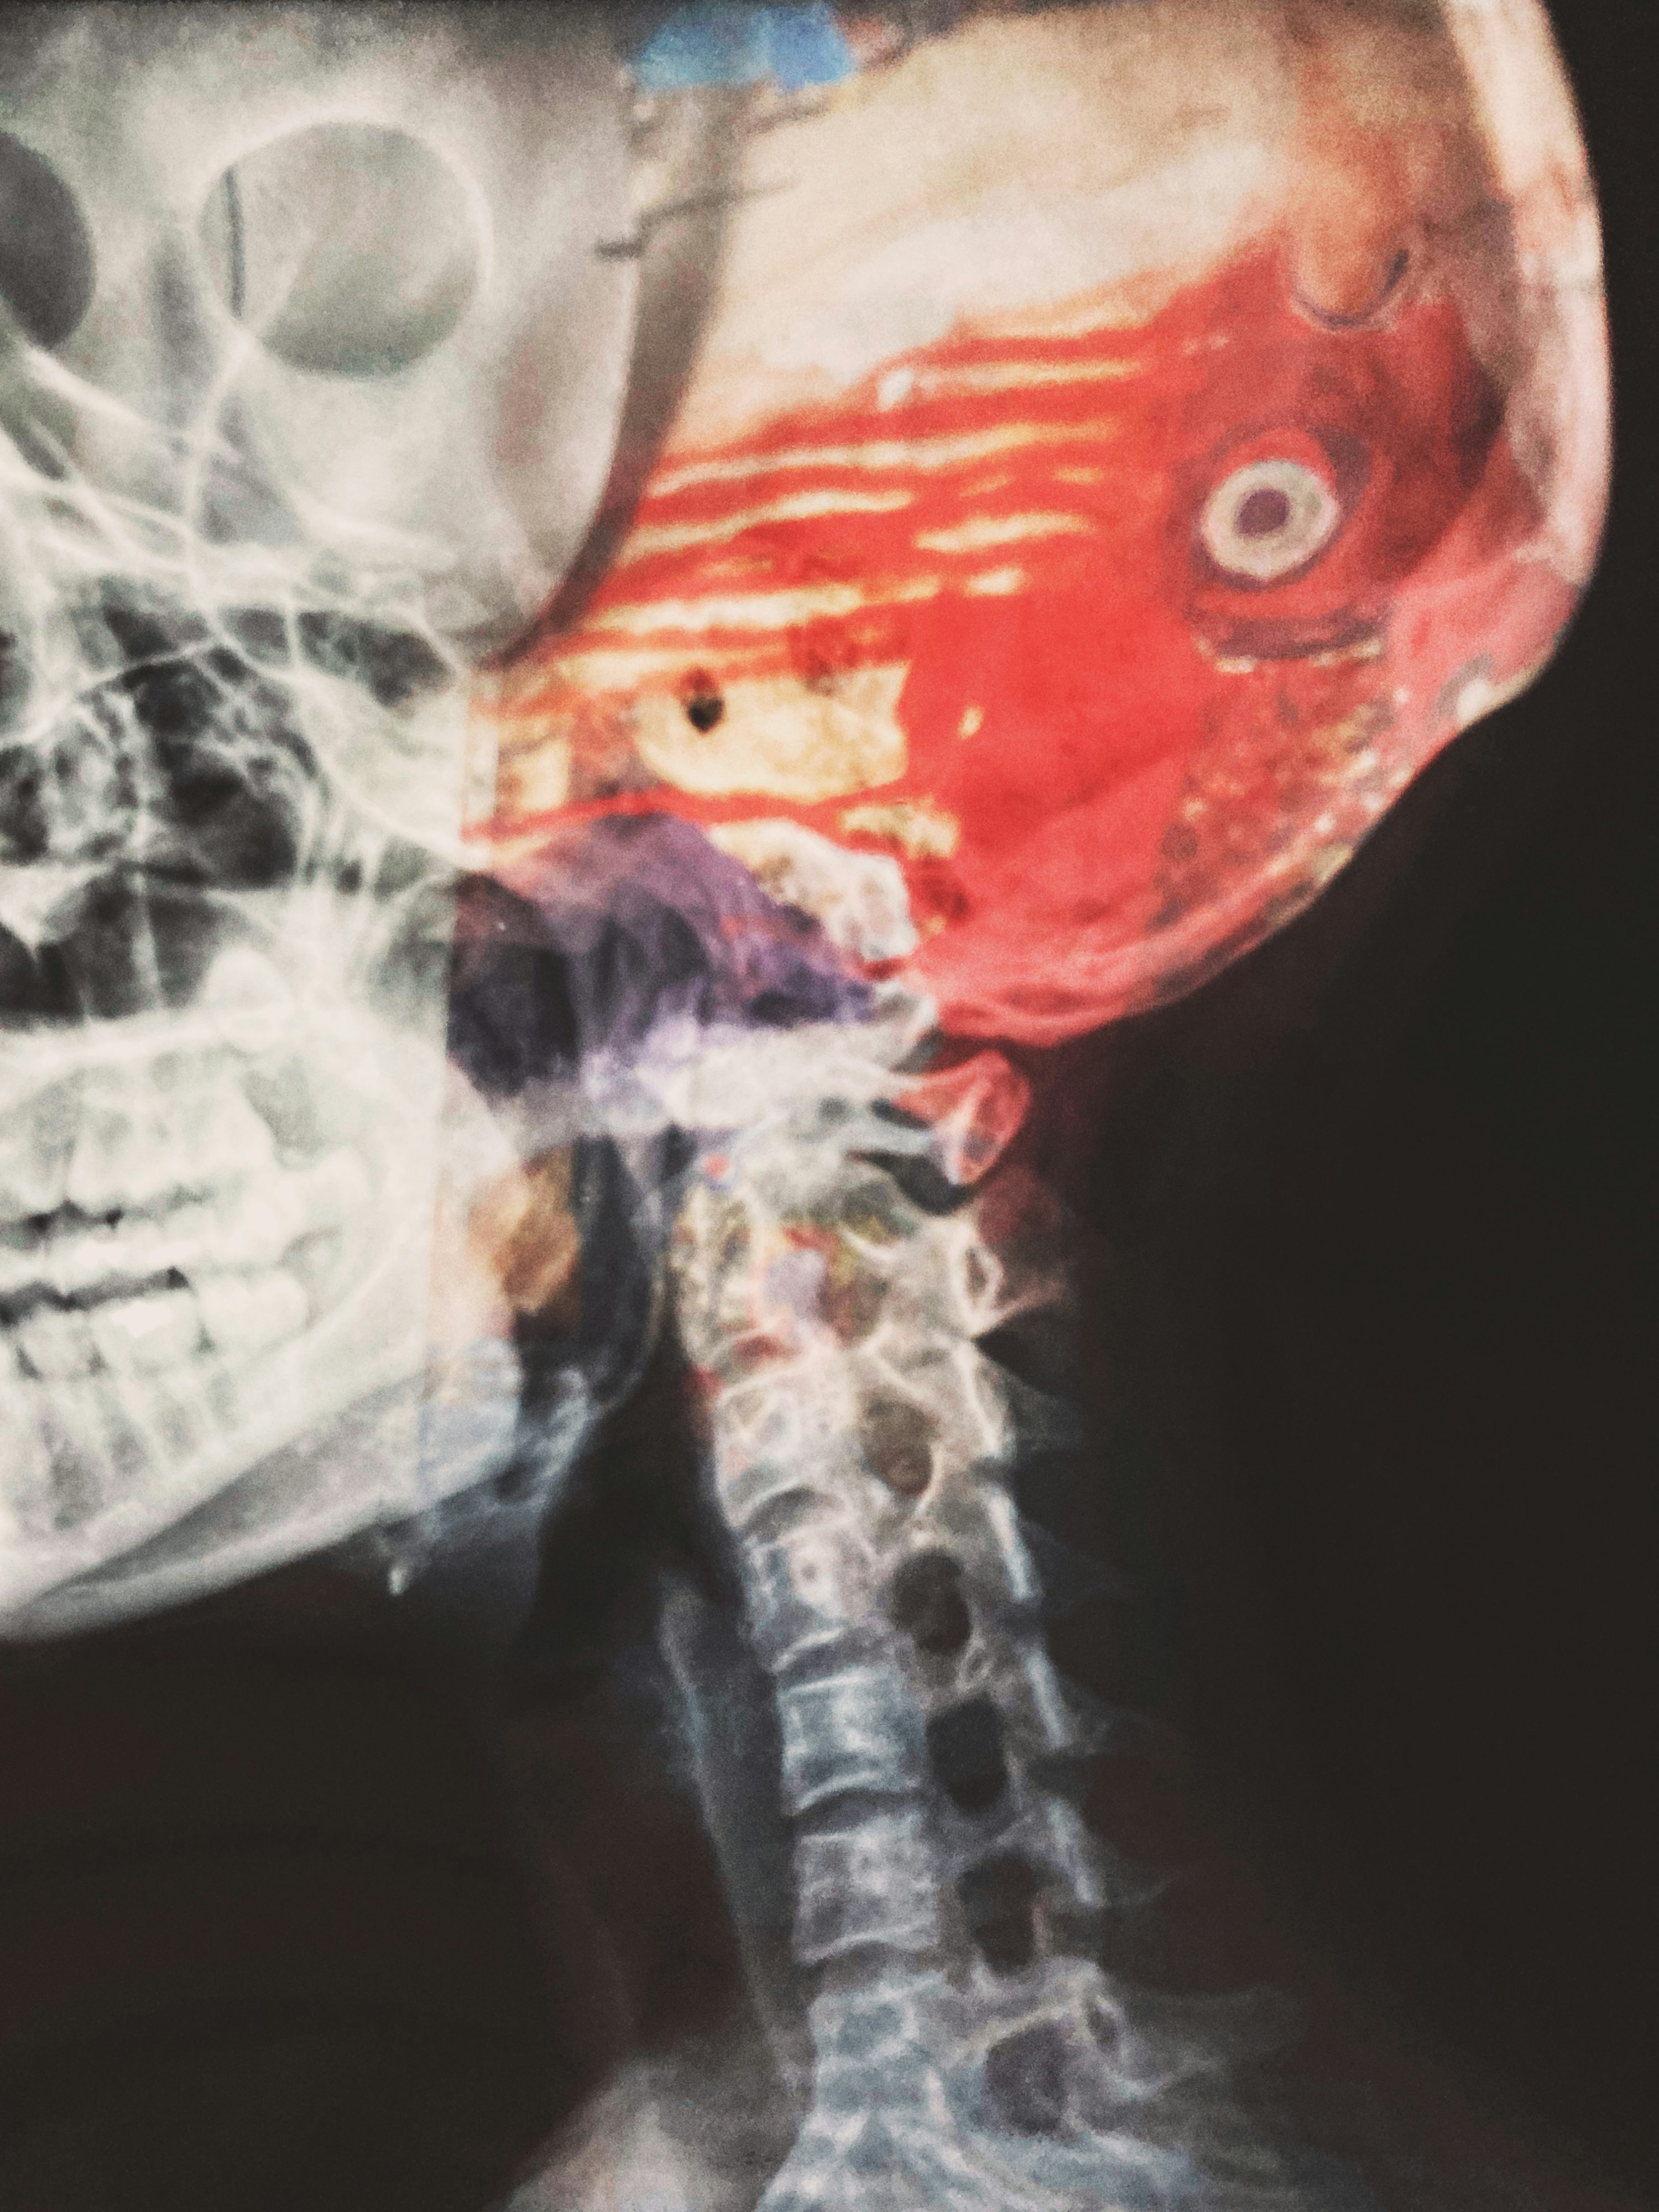

Q2. 뇌경색과 뇌출혈 초기증상은 어떻게 다른가요?

A. 두 질환의 초기증상은 매우 유사하여 증상만으로는 구별이 거의 불가능합니다. 다만 뇌출혈은 갑작스러운 극심한 두통, 구토, 의식 저하가 더 흔하고, 증상이 더 급격하게 악화되는 경향이 있습니다. 하지만 정확한 진단은 병원에서 CT나 MRI 검사를 통해서만 가능하므로, 증상이 나타나면 즉시 응급실로 가야 합니다.